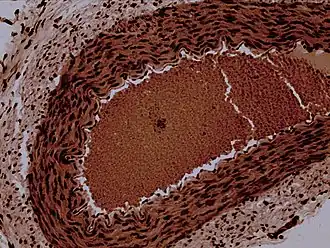

![]() Rabbit arteriole at 100X | |